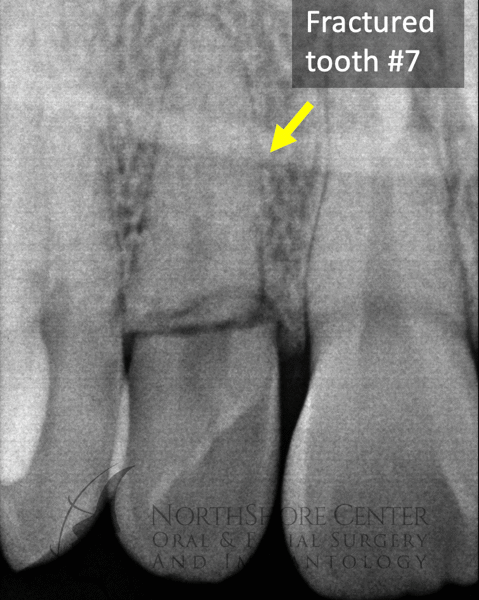

Losing a front tooth can be particularly stressful and traumatic for patients. Oftentimes when a front tooth needs to be removed you have to wear a removable device (a “flipper” or “essix retainer”) to hide the missing tooth. At NSCOFS we have refined the technique of immediate implant placement with a temporary crown so oftentimes you never have to go without your tooth and don’t have to wear a bulky removable device.

For patients with a big smile, immediate temporary crowns also preserve your natural soft tissue, preventing the appearance of gum recession and tissue defects.

case 1: Fractured Tooth #7 on an 18-year old Male